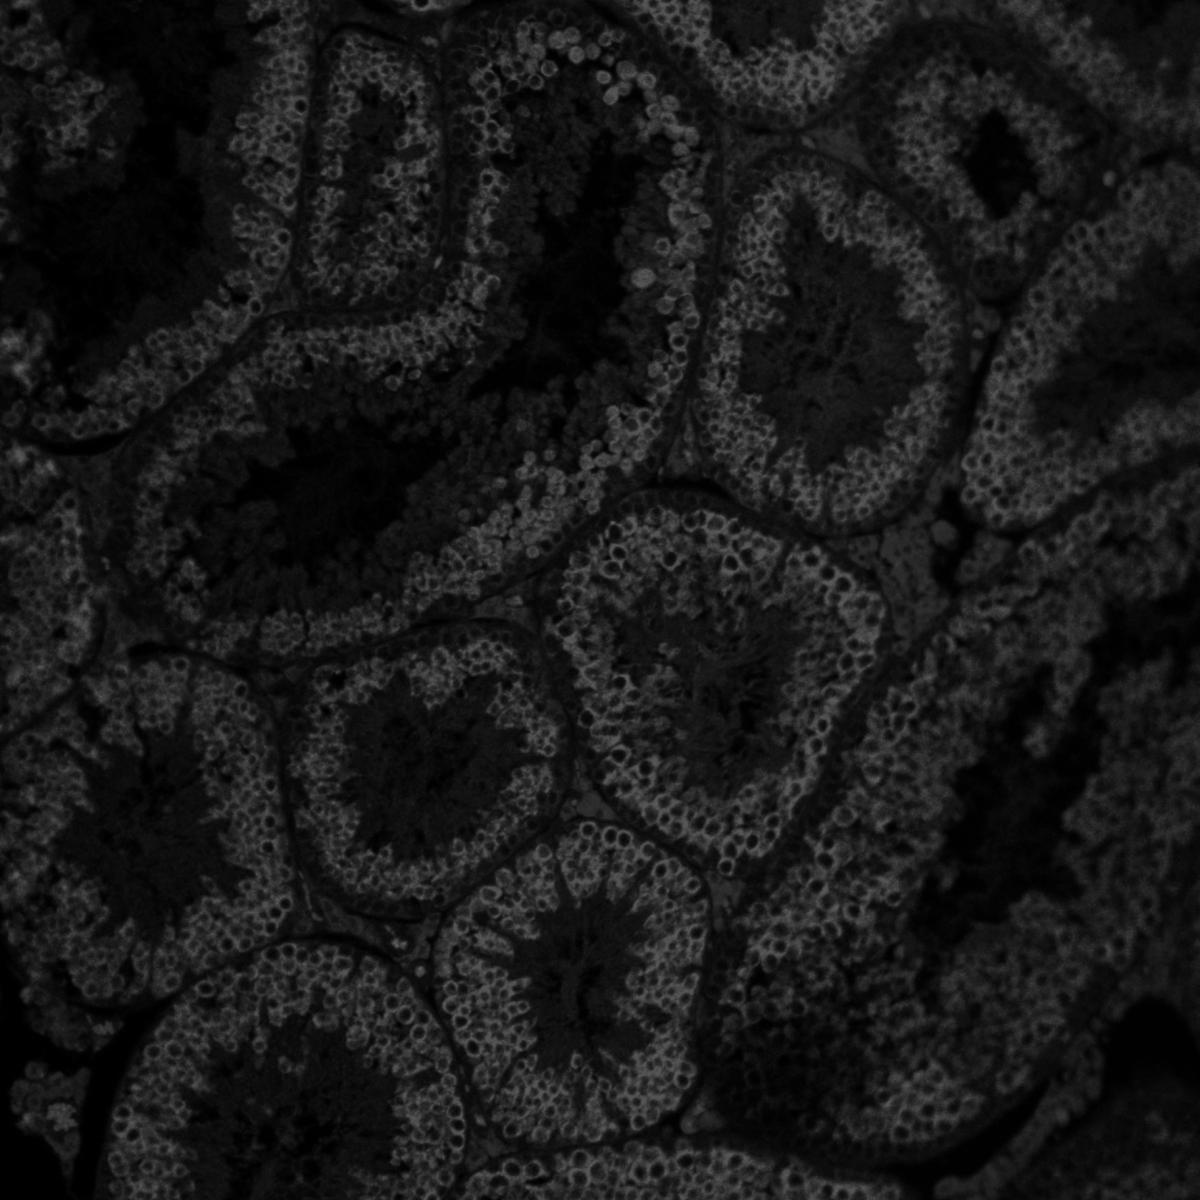

Clark’s research has yielded critical insights into the cell and molecular principles of human primordial germ cell development during prenatal life. Her lab uses human embryonic stem cells to model and understand the molecular and genetic events that regulate the production of germ cells, which create eggs or sperm. Through this work, she seeks to characterize the key stages of healthy germ cell development and to discover the genes, pathways and environmental factors that can disrupt this process, ultimately causing infertility and reproductive aging.

- Building stem cell-based models to investigate the mechanisms that control ovarian follicle formation, ovarian function and ovarian aging